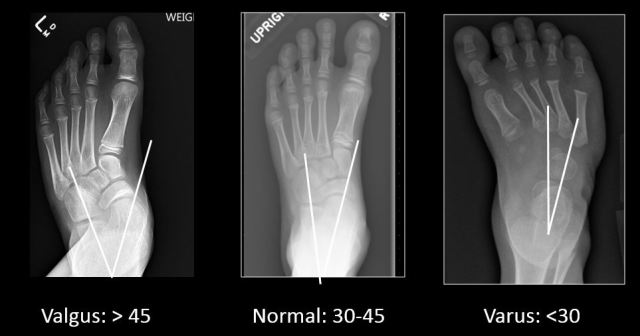

- Talocalcaneal angle: the angle formed between midtalar and midcalcaneal line. Normal: 300-450; <300: varus; >450: valgus.

- Valgus: increase in talocalcaneal angle (>450) with midcalcaneal line deviated away from midline.

- Varus: decrease in talocalcaneal angle (<300) with midcalcaneal line deviated towards midline (r in the va’r’us is for ‘reduction’ of angle).

Valgus and varus are best evaluated on AP view while equinus, calcaneus and cavus are best evaluated on lateral view.